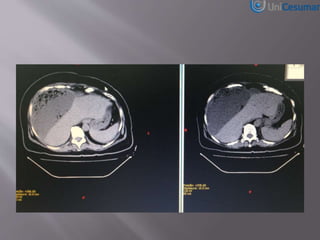

Tomografia Computadorizada

(1)Apendicite Aguda

(1) Pancreatite Aguda

(2) Níveis Hidroaéreos

RX TORAX ELEVAÇÃO CUPULA DIAFRAGMATICA DIREITA

COM CONDENSAÇÃO PULMONAR OU PNEUMOPERITONEO?

TC ABD – ABCESSO HEPATICO

GIGANTE

Historia pregressa:

•Colecistectomia há 4 anos.

•Internada HSR com icterícia e elevação

das transaminases.

•CT Abdome com discreta dilatação das

vias biliares intra-hepáticas.

•CPRE com papilotômia e retirada de 01

calculo impactado colédoco.